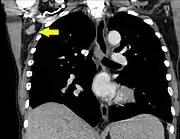

| Лімфаденопатія пахвових лімфатичних вузлів на зрізі комп'ютерної томограми (показана жовтою стрілкою) | |